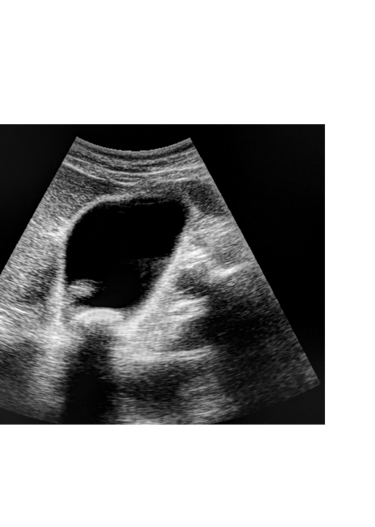

Ecografia addominale: è il metodo diagnostico di prima scelta per visualizzare i calcoli all'interno della colecisti. È non invasiva, veloce ed efficace.